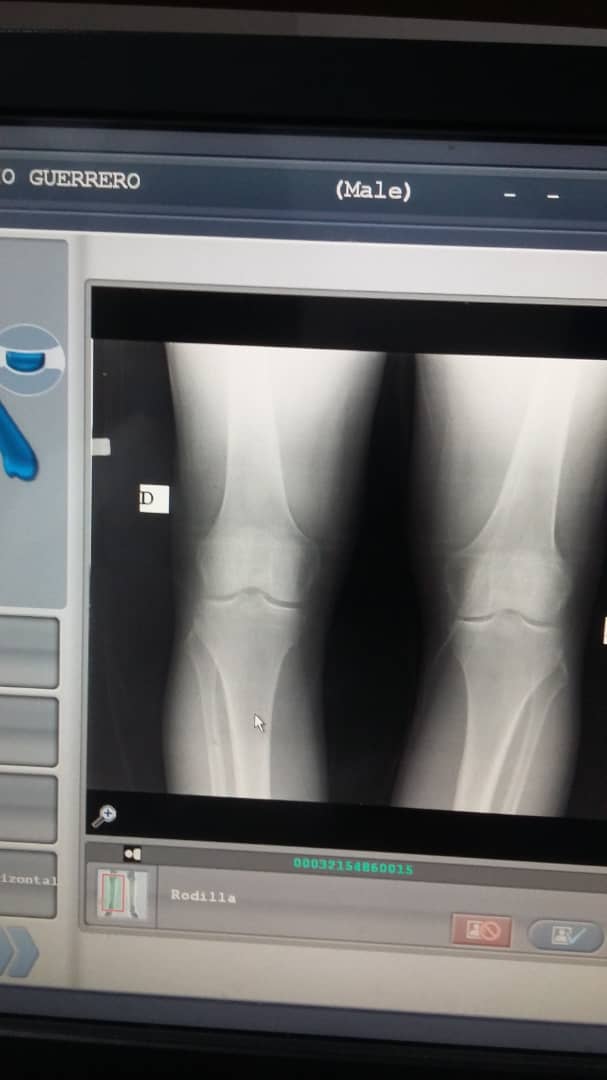

El periodista Mario José Guerrero Urdaneta presenta actualmente una artrosis bilateral, a consecuencia del desgate de cartílago en la rodilla izquierda.

Para cumplir con su tratamiento, necesita realizarse una infiltración articulatoria de tres ampollas de ácido hialurónico en la rodilla; pero no tiene los recursos económicos como para costear el tratamiento.